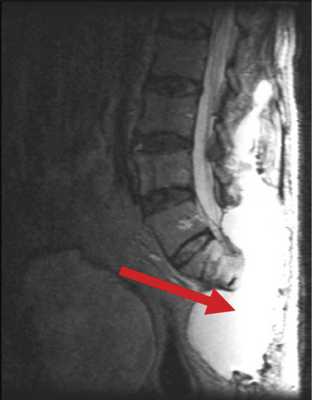

В случае пациента Б., 78 лет, после высокой ампутации крестца, в блок опухоли вошла часть m. erector spinae. Для пластики дефекта были использованы большие ягодичные мышцы, левый лоскут был частично развернут. У пациента наблюдался дефицит массы тела, развившийся на фоне выраженного болевого синдрома, который, в частности, сопровождал акт дефекации. В связи с этим пациент старался меньше есть, за счет чего масса тела снизилась с 86 до 65 кг за 1 мес. Нарушение репаративной функции привело к отсутствию сращения мягких тканей, сформировалась полость, заполненная серозной жидкостью, общим объемом около 5 л (рис. 3). Рис. 3. Гигантская серозная полость как осложнение сакрэктомии (указана стрелкой).

Для лечения подобных осложнений используется метод транспозиции ректоабдоминального лоскута в пресакральную область ректоабдоминальным доступом (рис. 4). Рис. 4. Пример использования метода транспозиции ректоабдоминального лоскута на питательной ножке. а — МРТ больного после операции, сагиттальная проекция. Перемещенный дедерматизированный ректоабдоминальный лоскут указан стрелкой; б — схематическое изображение перемещения лоскута.